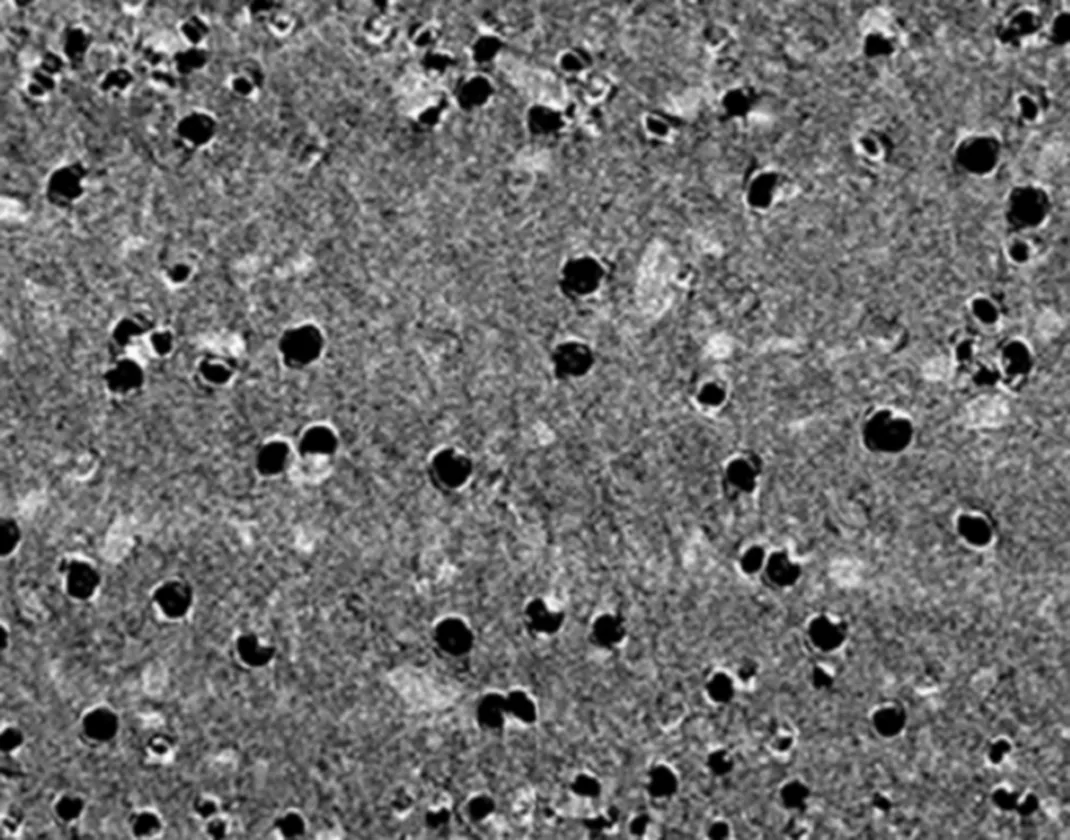

For effective resolution of regional subacute inflammation and prevention of biofouling formation, we have developed a polymeric implant that can release meloxicam, a selective cyclooxygenase (COX)-2 inhibitor, in a sustained manner. Meloxicam-loaded polymer matrices were produced by hot-melt extrusion, with commercially available biocompatible polymers, poly(ε-caprolactone) (PCL), poly(lactide-co-glycolide) (PLGA), and poly(ethylene vinyl acetate) (EVA). PLGA and EVA had a limited control over the drug release rate partly due to the acidic microenvironment and hydrophobicity, respectively. PCL allowed for sustained release of meloxicam over two weeks and was used as a carrier of meloxicam. Solid-state and image analyses indicated that the PCL matrices encapsulated meloxicam in crystalline clusters, which dissolved in aqueous medium and generated pores for subsequent drug release. The subcutaneously implanted meloxicam-loaded PCL matrices in rats showed pharmacokinetic profiles consistent with their in vitro release kinetics, where higher drug loading led to faster drug release. This study finds that the choice of polymer platform is crucial to continuous release of meloxicam and the drug release rate can be controlled by the amount of drug loaded in the polymer matrices.